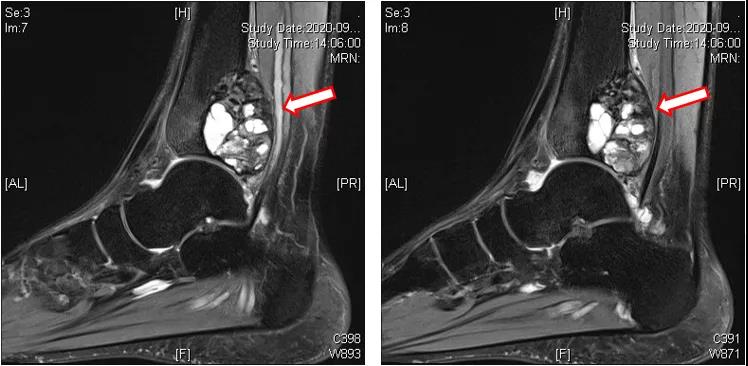

辅助检查:左踝MRI(2020-09-03):左侧胫骨内侧髁关节面下见团块状T1WI等信号、T2压脂不均匀高信号影,内见多发囊腔;病变大小约为27 mm(前后)×39 mm(左右)×45 mm(上下),边界清楚,病变后缘向后膨隆,周围软组织见条片状压脂高信号影(T2WI脂肪抑制序列病变周边高信号),环绕胫骨下端周长2/3。左侧胫骨内侧髁关节面下占位性病变,考虑骨巨细胞瘤可能性大(图1~3)。

图1:左踝MRI(2020-09-03)

图2:左踝MRI(2020-09-03)